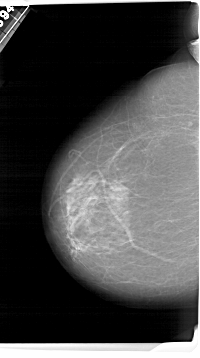

A_1495_1.RIGHT_MLO

RIGHT_MLO LINES 6871 PIXELS_PER_LINE 4186 BITS_PER_PIXEL 12 RESOLUTION 43.5 OVERLAY